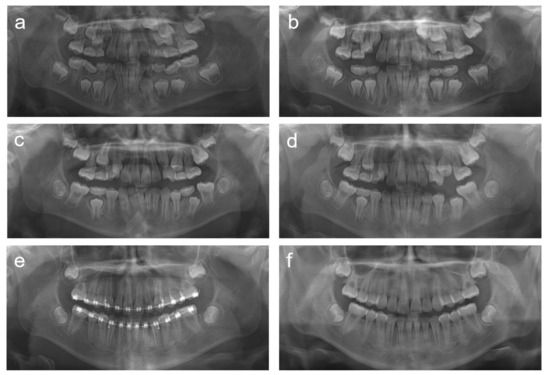

2.1. Case 1

2.2. Case 2

2.3. Case 3

2.4. Case 4

2.5. Case 5